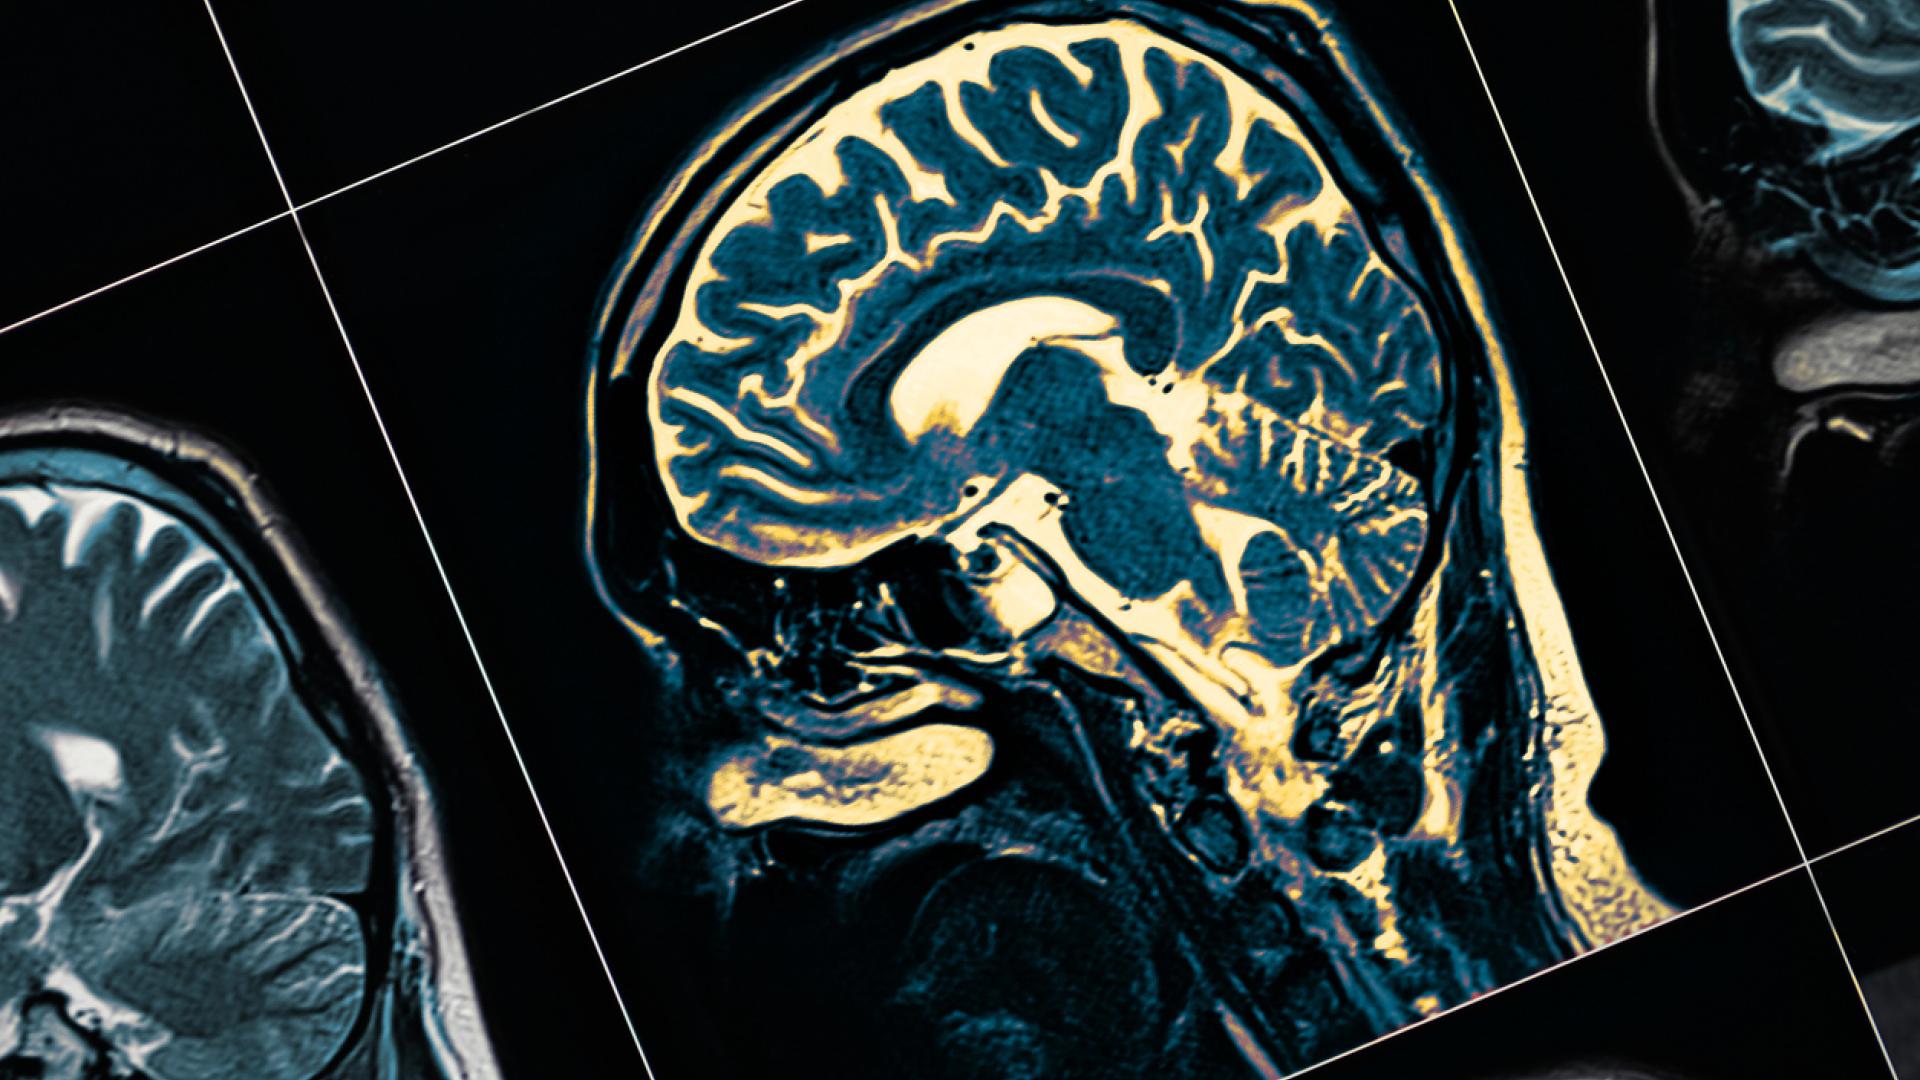

Researchers from Yale School of Medicine have discovered a promising new drug compound that reverses some Alzheimer’s effects on memory in mice.

They found that a protein drug compound, known as TC-2153, blocks the Alzheimer’s disease linked effects of another protein called striatal-enriched tyrosine phosphatase (STEP). At high levels, STEP prevents synaptic strengthening in the brain—something vital to memory function.

Since their discovery of STEP, Lombroso and his team have been searching for a drug that would block its damaging effects on brain synapses. It was already known that STEP levels increase in Alzheimer’s disease due to beta amyloid buildup. As beta amyloid accumulates in the cells, it inhibits the cellular functions that would destroy excess levels of STEP. To make matters worse, STEP is also implicated in allowing beta amyloid’s entry into neurons. While this study has particular relevance to Alzheimer’s disease, STEP is tied to other neurological disorders as well, including schizophrenia, Parkinson’s disease, and fragile X syndrome.

The latest accomplishment was to show their lead molecule, TC-2153, binds tightly to STEP molecules and thus, even in the presence of high STEP levels, blocks the protein’s destructive effect on neural synapses. Treating mice with a single dose of TC-2153 improved their cognitive function.